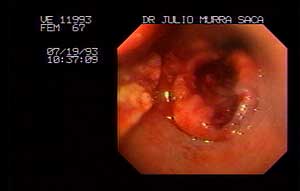

Femenino sesenta y siete años carcinoma del tercio medio del esófago al momento del examen endoscopico tenía masa en el flanco derecho, presentaba disfagia progresiva primero a sólidos y luego a líquidos .